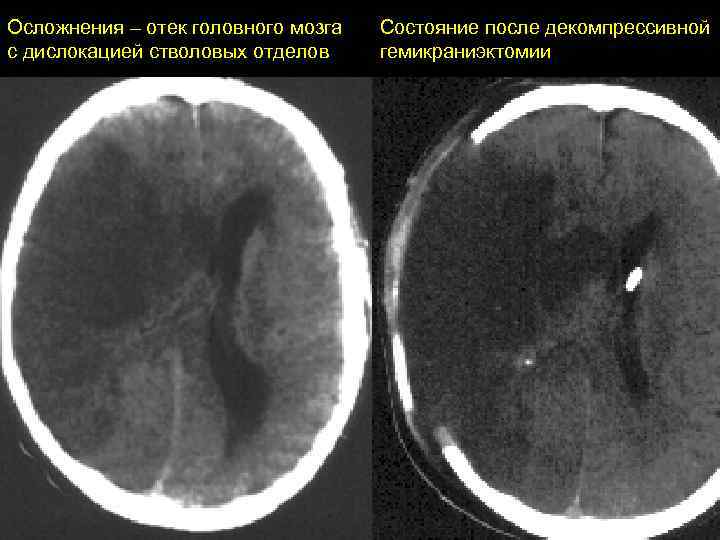

Осложнения – отек головного мозга с дислокацией стволовых отделов Состояние после декомпрессивной гемикраниэктомии